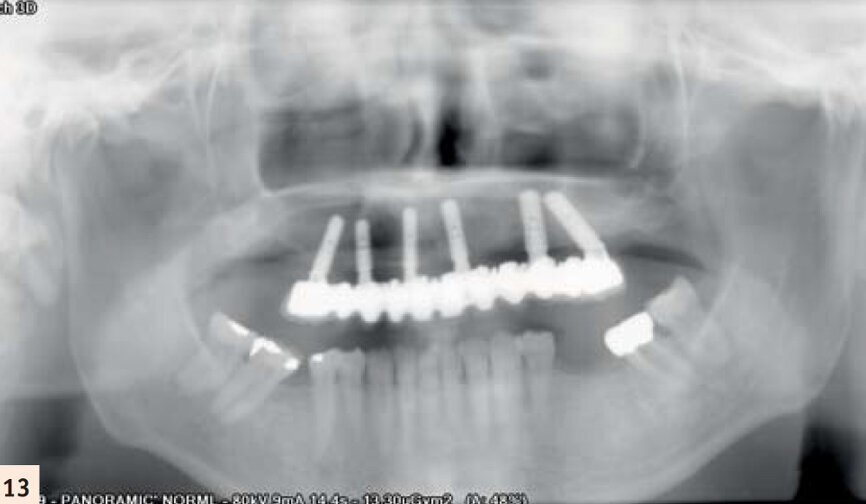

Elle porte un appareil amovible au maxillaire, côtoyant 5 dents naturelles. Elle souhaite une solution fixe (Figs. 1, 2, 3). Après empreintes, mise en articulateur et confection d’un guide radiologique, un examen 3D est réalisé. L’analyse des fichiers DICOM’s transférés sur le logiciel de planification CoDiagnostiX, confirme un faible volume osseux.5Les sinus ont fortement pneumatisé le maxillaire et les parois antérieures sont au niveau des canines.

Stellite remplaçant 9 dents.